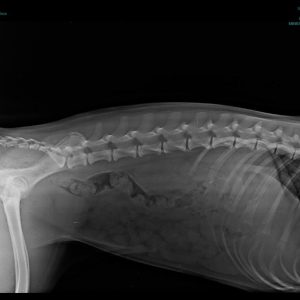

Füli kutyusunk egy jelenleg kb másfél éves, mentett, bántalmazott keverék, szuka kutyus (15 kg-os, vékony testalkatú, közepes magasságú, rövidszőrű keverék kutyus). Sérülése egy korábbi bántalmazásból eredt, mikor kiskutyaként husánggal úgy megverhették, hogy combnyaktörése lett. Ezt mi derítettük ki, mikor hozzánk került tavaly októberben. Akkor észrevettük, hogy aggasztóan sántít, és elvittük megröntgeneztetni. Több orvos véleményét is kikértem, és mindannyian azt tanácsolták, hogy műttessük meg (elég drasztikus műtéttel, a combcsontfej egy részét kivágták volna).

Molnár doktor úr egyedüliként, a röntgen kép alapján, arra bíztatott, hogy mivel a kutyus még növekedésének vége előtt állt, próbáljunk ki egy 3 hónapos csont- és porcépítő csomagot. Így is tettünk. Már kezdetben is nagy javulást észleltünk. Pár hét után el-elmaradozott a sántítás és szép lassan teljesen elmúlt. De természetesen nem elégedtünk meg ennyivel. Májusban az ivartalanítási műtét során kértem az orvost, hogy készítsen röntgenfelvételt Füli lábáról. A röntgen el is készült, és nagy örömünkre, már ez az állatorvos is azt mondta, hogy nincs szükség a combcsontfej műtétjére.